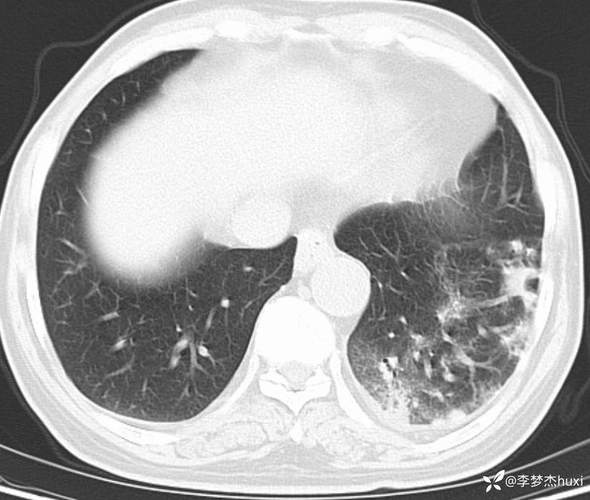

脑梗病人肺部感染症状

(图片来源网络,侵删)